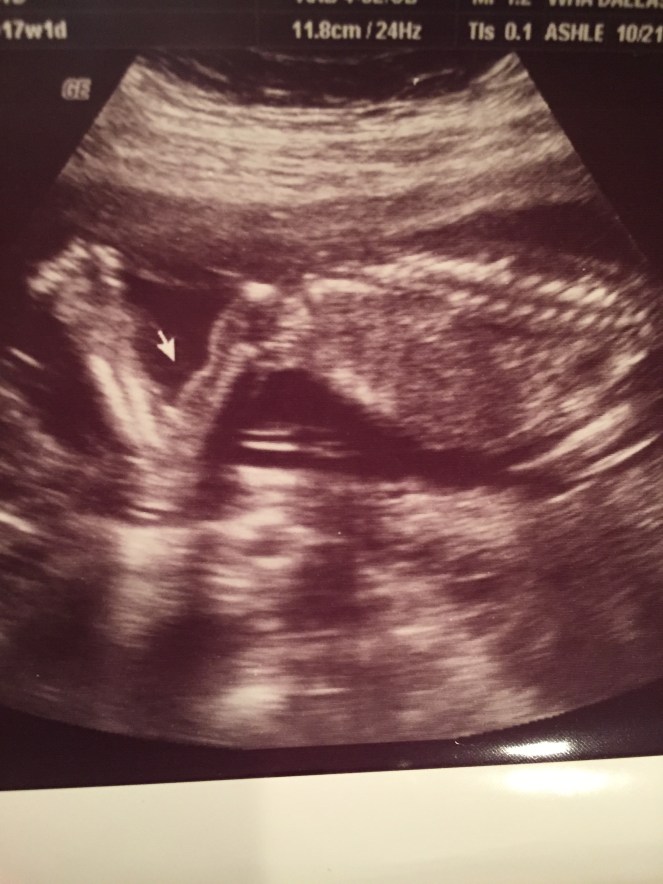

After the appointments are over, I am so emotionally drained. The relief of hearing his heartbeat and seeing him move is overwhelming. The fear that had been building is released and then thoughts or memories of Cora spring up. It can’t be helped, she is woven into this pregnancy with every big moment. Constantly comparing this pregnancy to my pregnancy with her. With her, I didn’t memorize all of the heartbeats or sizes. I didn’t really have the opportunity to do that because I did not have as many appointments. This time, I memorize everything. His heart rate last week was 150 bpm and he measured ahead in almost every category. His head measured 17w4d and his belly measured 17w6d, I was 17w1d at the appointment.